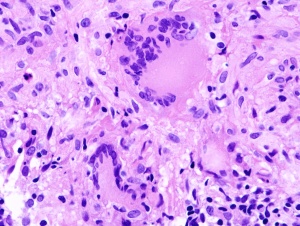

肺结核切片

肺结核切片,肺结核图片

免费文档 所有分类 高等教育 医学 医学病理学实验切片 63肺结核

病理切片